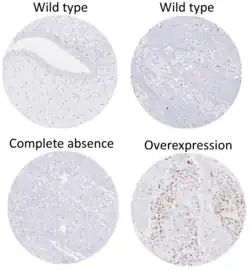

Diagnostic and prognostic significance

This image shows different patterns of p53 expression in endometrial cancers on chromogenic immunohistochemistry, whereof all except wild-type are variably termed abnormal/aberrant/mutation-type and are strongly predictive of an underlying TP53 mutation:[92]